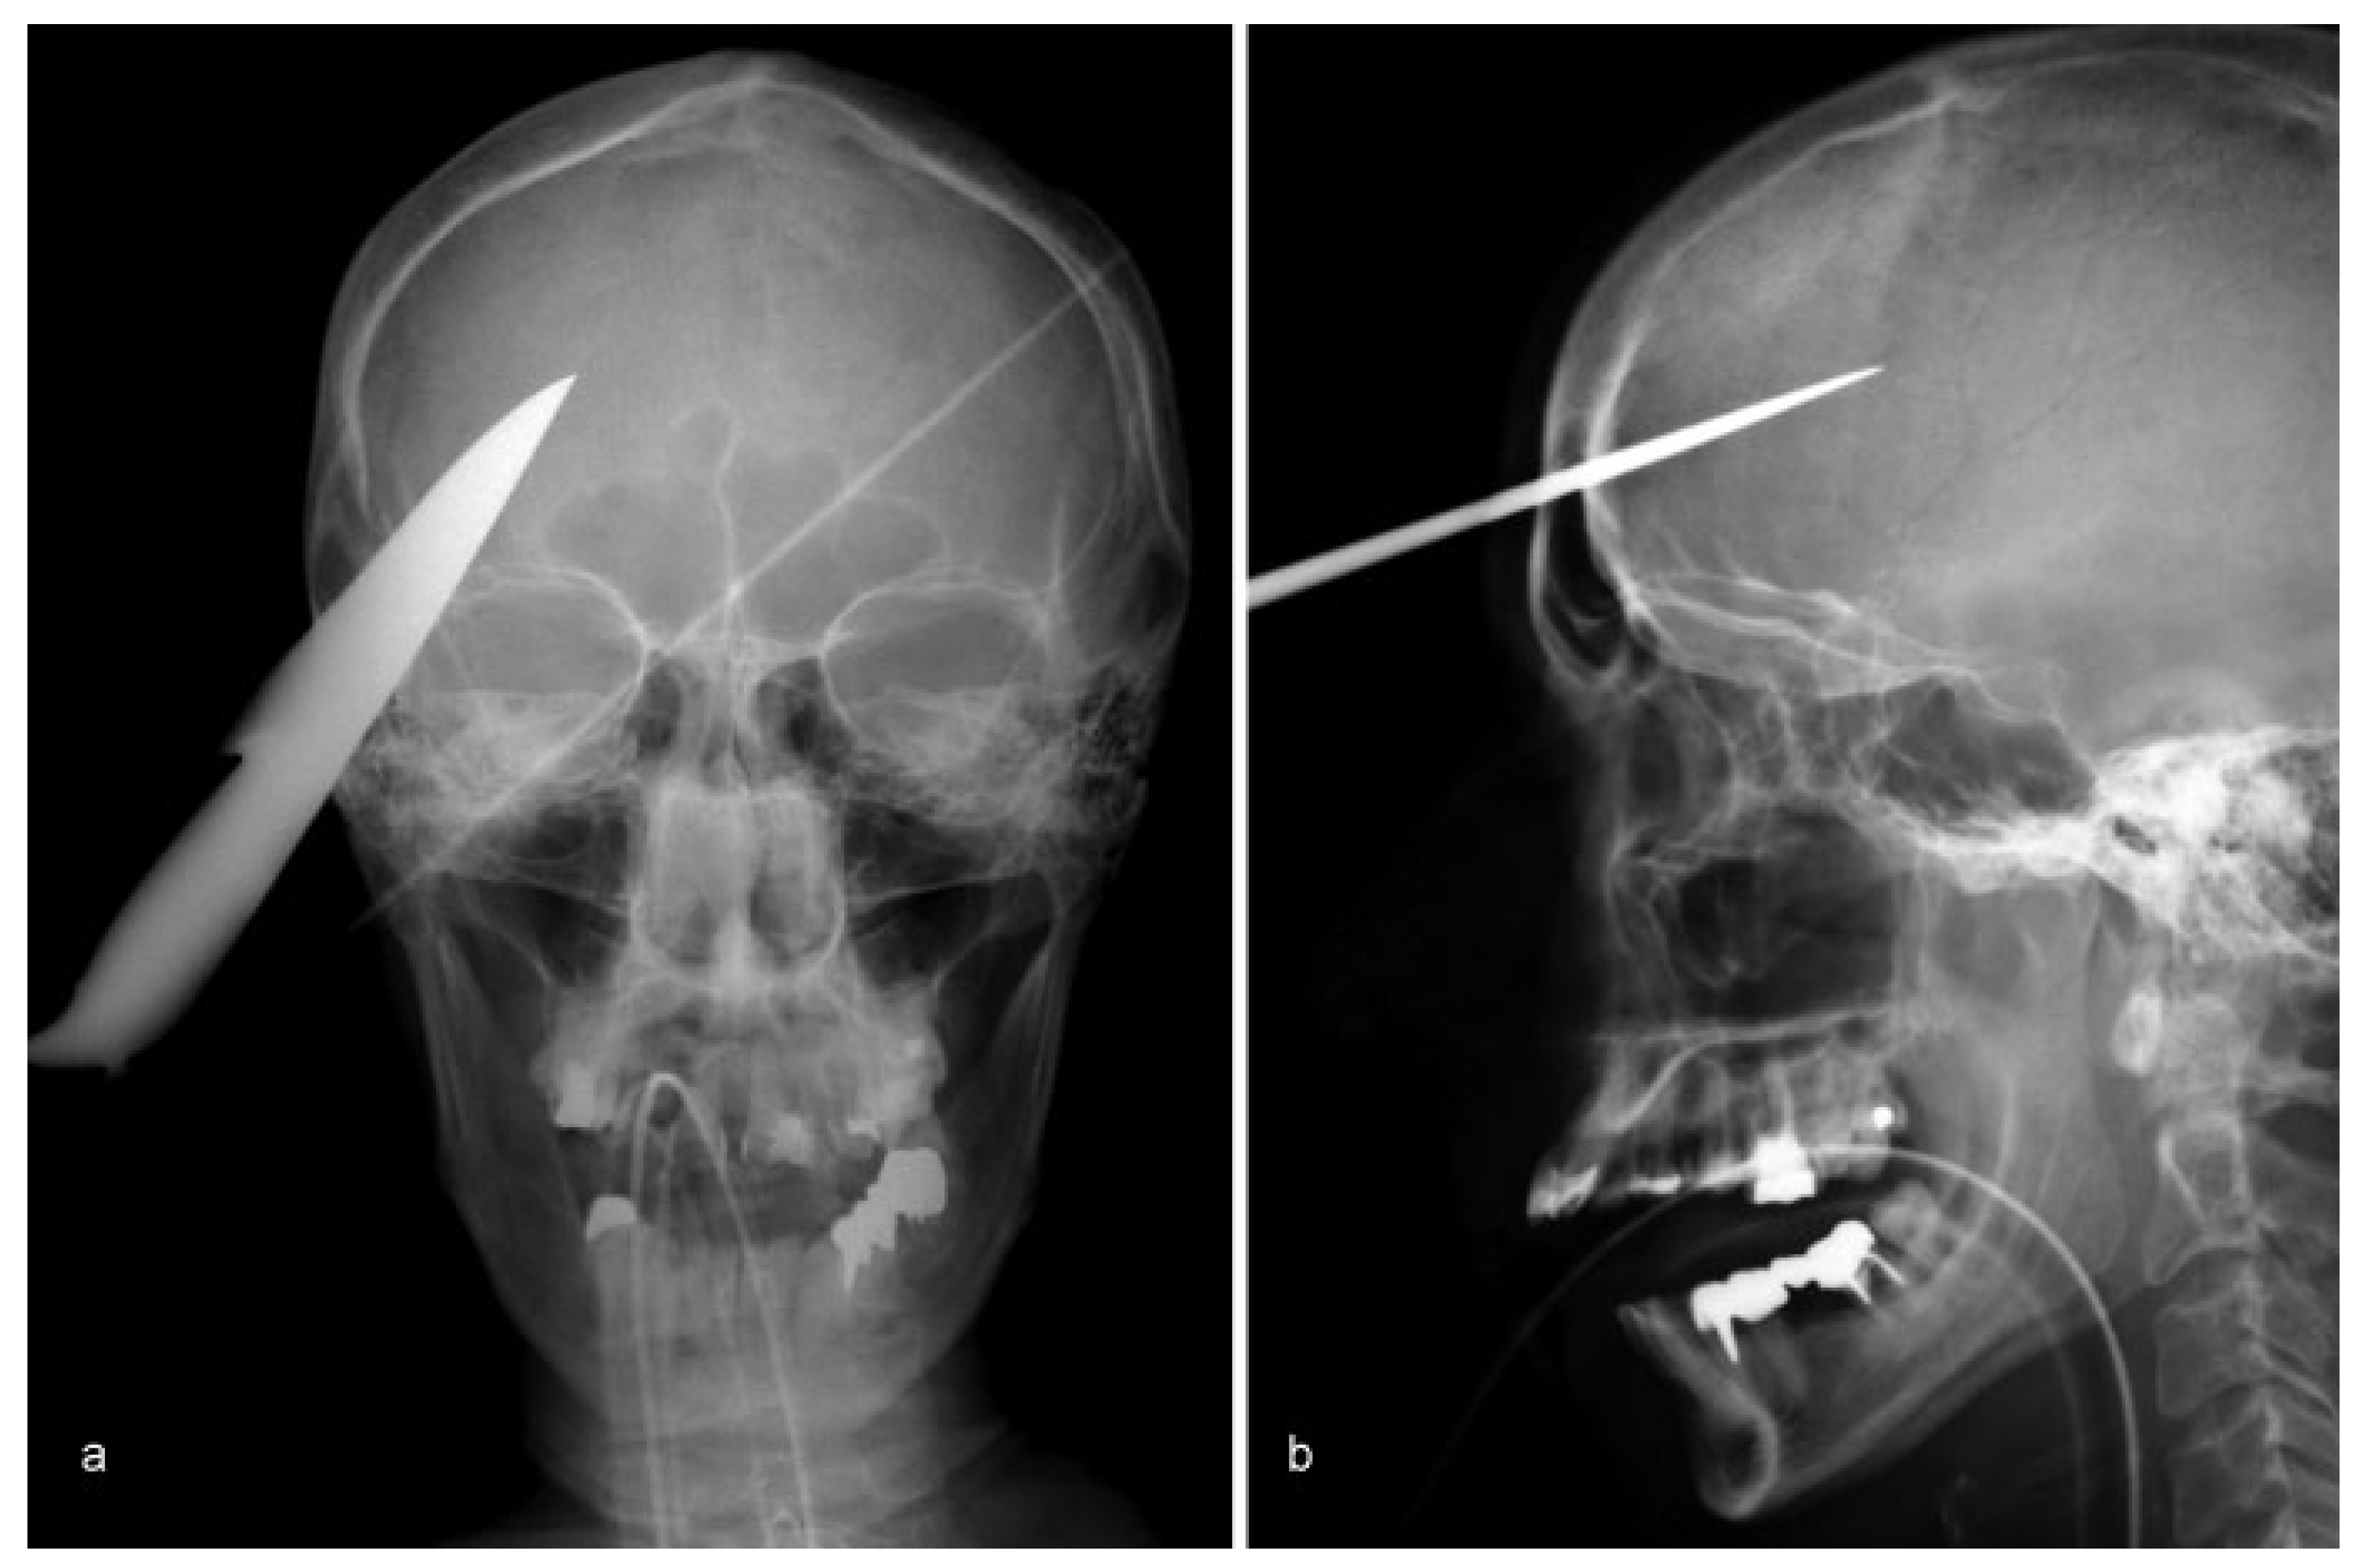

• Case 7: Another impalement injury, also known as a Jael’s syndrome [8], was presented by a 38-year-old psychiatric patient who had attempted to commit suicide by stabbing himself in the face with a knife. Clinical examination and radiological imaging of the patient displayed an intracranial penetrating stab injury, which had entered the neurocranium supraorbitally (Figure 7a,b). The impacted knife was removed via craniotomy and dura repair in cooperation with the neurosurgery department. No injury to the greater intracranial vessels was detectable. Postoperative wound healing proceeded without any complains.

Figure 7. (a,b) Lateral and frontal skull radiographs showing a radiopaque foreign body penetrating into the neurocranium.